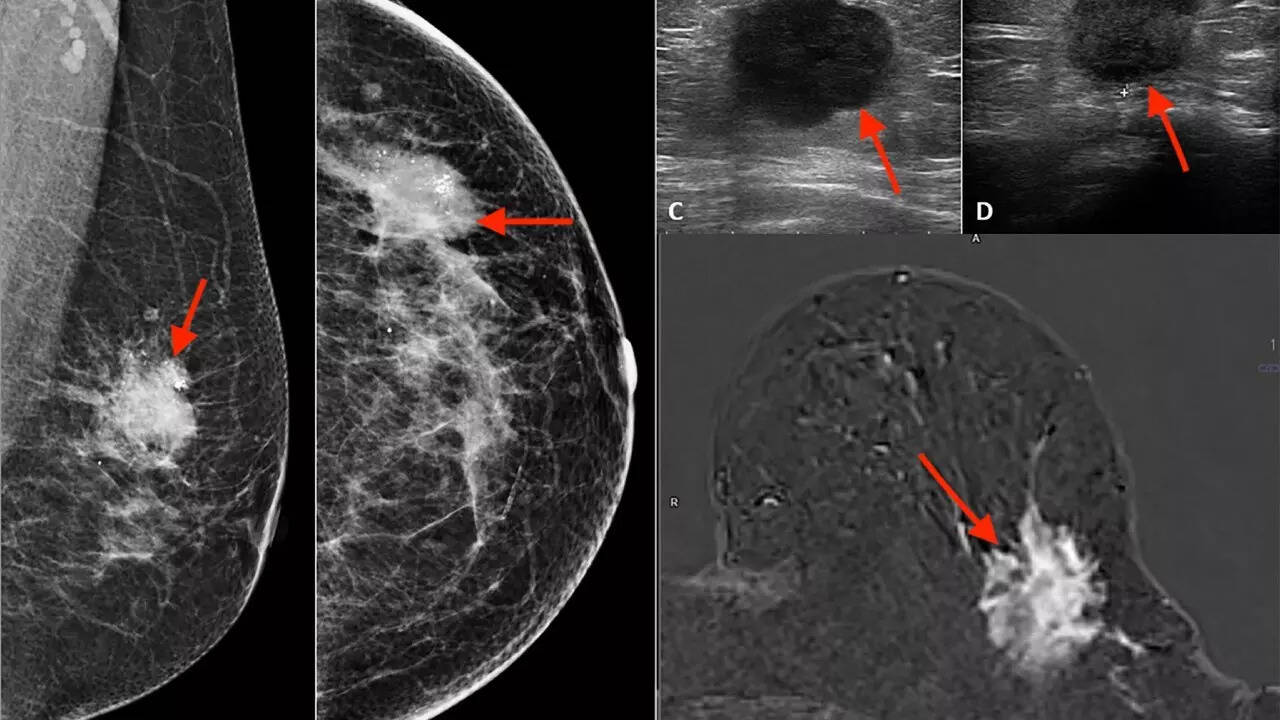

Breast cancer, one of the most aggressive kinds of cancer, remains the most commonly diagnosed cancer among women globally. Not to say that men are safe from this kind of cancer, but in 2022 alone, around 2.3 million women were diagnosed with the disease, and approximately 670,000 died. The more concerning part? The World Health Organization (WHO) has projects that, if current trends continue, both incidence and mortality will rise by about 40% by 2050 in many regions, including those with limited health infrastructure.But turns out, the traditional breast cancer isn’t the only concern now.A lesser-known form of breast cancer is quietly rising in the United States, and it’s raising concerns in patients. It’s invasive lobular carcinoma. Unlike the familiar ductal breast cancer, ILC behaves differently and can be harder to detect early. With projections estimating some 33,600 new ILC cases this year, experts are warning that awareness, recognition of warning signs, and tailored care must increase.A rising breast cancer subtype: Invasive Lobular CarcinomaAccording to a new report from the American Cancer Society, approximately 33,600 women in the US are expected to be diagnosed this year with invasive lobular carcinoma (ILC). What’s striking is that ILC incidence has been climbing at about 2.8% per year from 2012 to 2021 – much steeper than the approximately 0.8% annual rise seen for other breast cancers.ILC originates in the lobules (milk-producing glands) and often behaves differently than the more common invasive ductal carcinoma (IDC). Its growth is typically more diffuse and less likely to form a firm, well-defined tumor, which can delay detection. Strikingly, although ILC accounts for just over 10% of breast cancer cases, its long-term outcomes may lag behind IDC in metastatic or advanced disease. Experts warn that ILC’s subtle presentation contributes to underdiagnosis and slower therapy responses. Because of its stealthy behavior, many ILCs are diagnosed later or discovered only via imaging or biopsy, rather than being felt as a lump.

There are a few possible reasons. While no single cause is confirmed, several factors may have contributed to the surge:Screening and detection patterns: Traditional mammograms sometimes miss ILC’s diffuse growth, leading to later diagnoses. As imaging improves (e.g., MRI, tomosynthesis), more cases may be found.Hormonal exposures: Like many breast cancers, ILC is often hormone receptor–positive, meaning long-term estrogen exposure may play a role.Population aging and hormone therapy: As more women live longer or use menopausal hormone therapy, the incidence of hormone-sensitive cancers may rise.Genetic and molecular changes: Some gene variants (e.g., in CDH1, linked to lobular cancer risk) could be relevant to this subtype.Lifestyle and environment: Obesity, alcohol, delayed childbirth, or fewer pregnancies – all known general risks – may also influence ILC incidence.At the moment, the rising trend of ILC is considered a warning – prompting more research, improved screening, and increased public awareness.